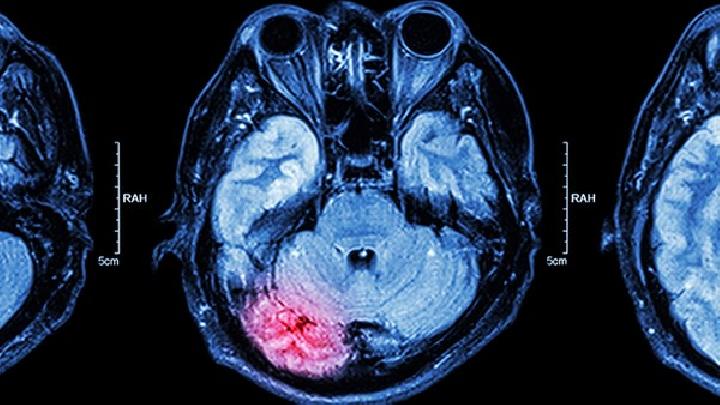

脑血管畸形

脑血管畸形的出现病因是什么